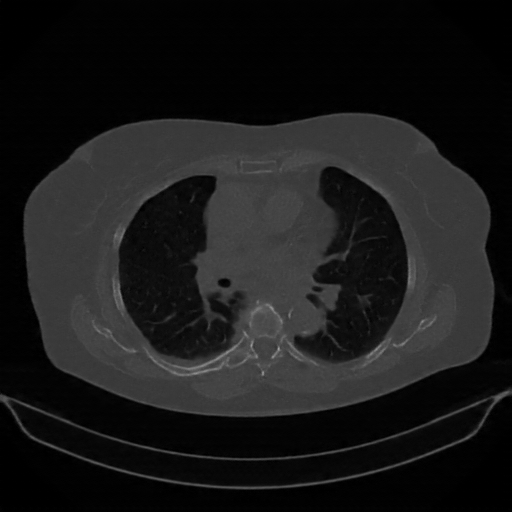

Original NATIVE CT scan (input)

No window - Raw intensity values

Lung window (WL -600, WW 1500 β†’ Low βˆ’1350, High +150)

Mediastinum window (WL 40, WW 400 β†’ Low βˆ’160, High +240)